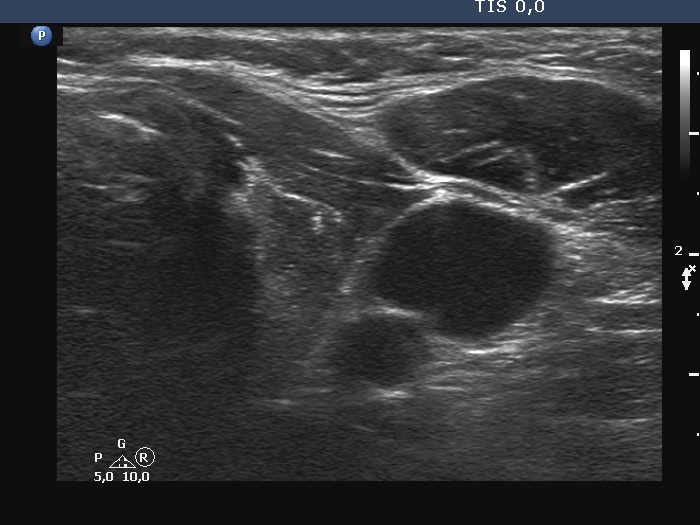

Ultrasonography. The thyroid was minimally hypoechoic. There were two discrete lesions in the left lobe. The larger has microcalcifications and irregular borders. The dimensions of this nodule were 9x11x12 mm (width, depth, length, respectively). The nodule had scanty intranodular vascularity.

Cytology resulted in papillary cancer.

A left lobectomy and left neck dissection were performed. Histopathology disclosed a T1b papillary cancer. No metastatic lymph nodes were found.